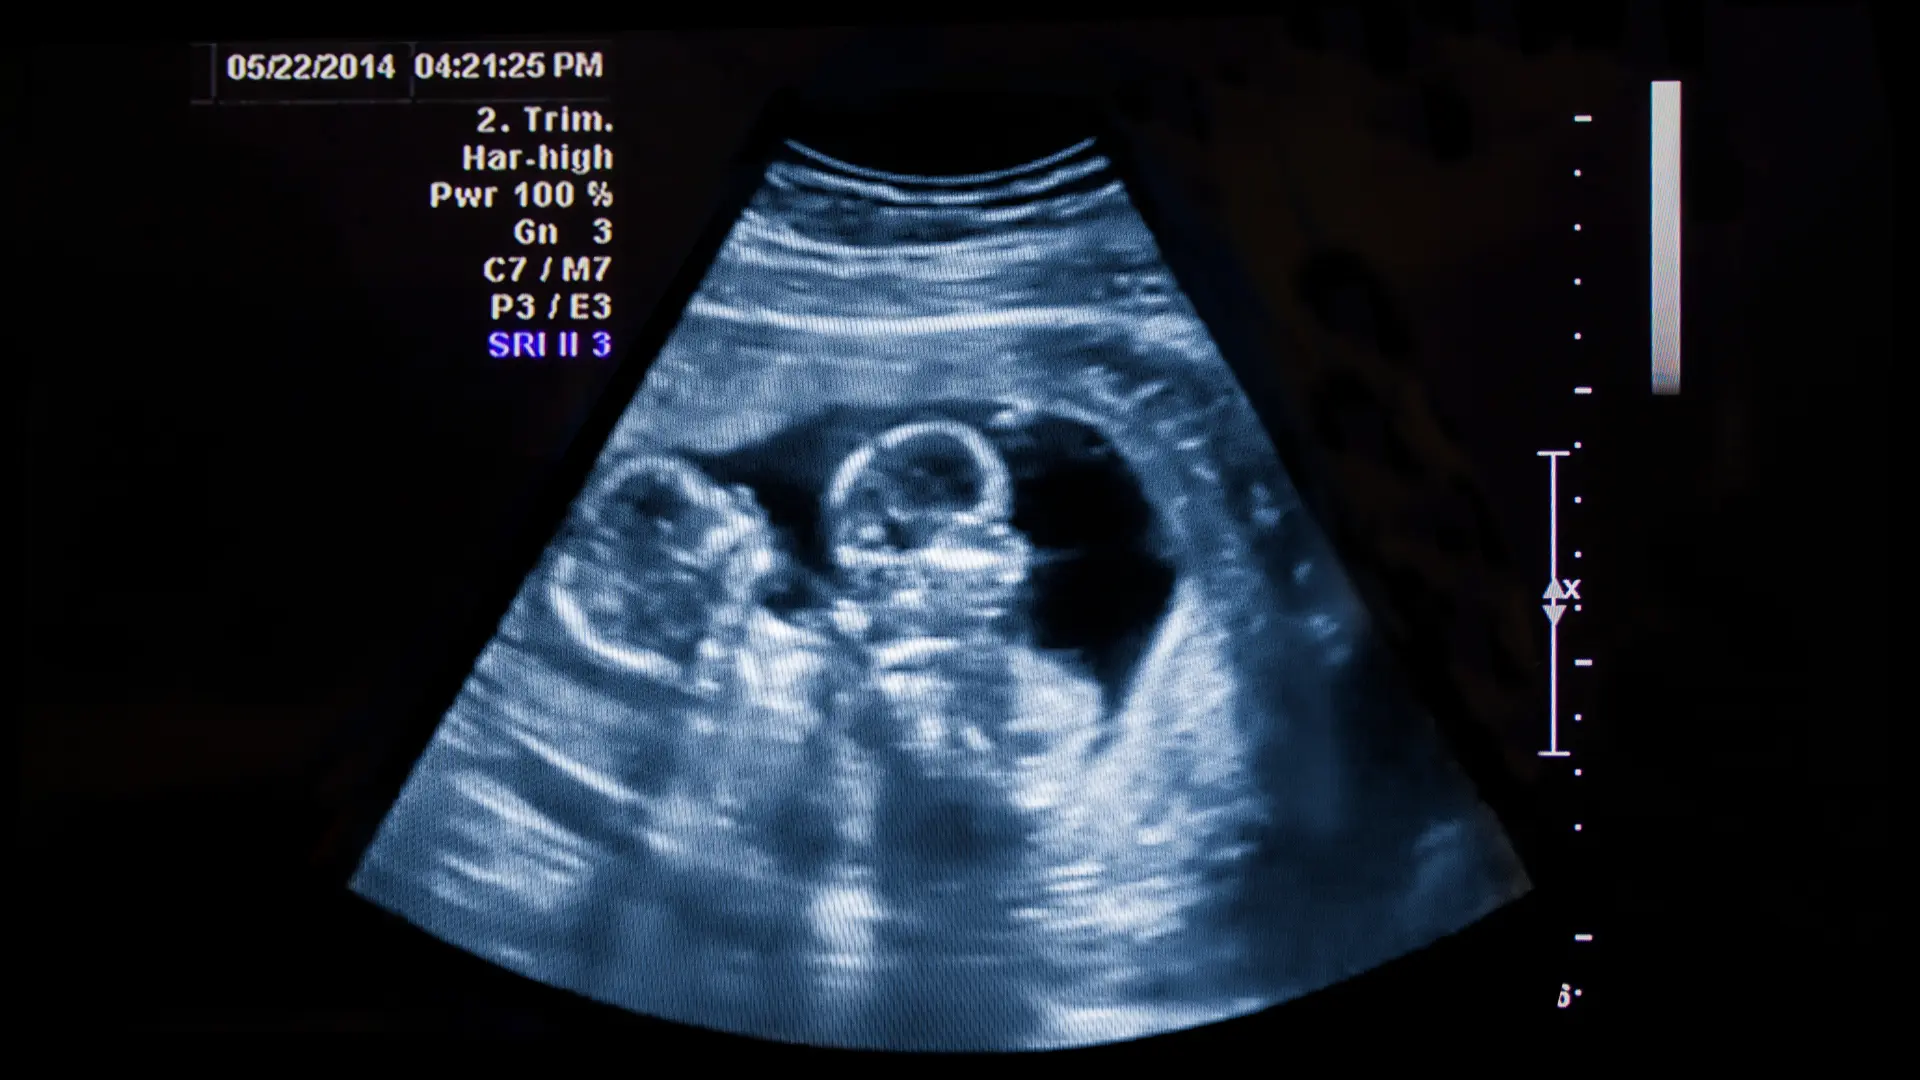

USG prenatalne ciąży bliźniaczej - dopłata za badanie drugiego płodu

Dodatkowa opłata za badanie ultrasonograficzne drugiego płodu w przypadku ciąży bliźniaczej. Dotyczy każdego z badań prenatalnych (I, II, III trymestr).